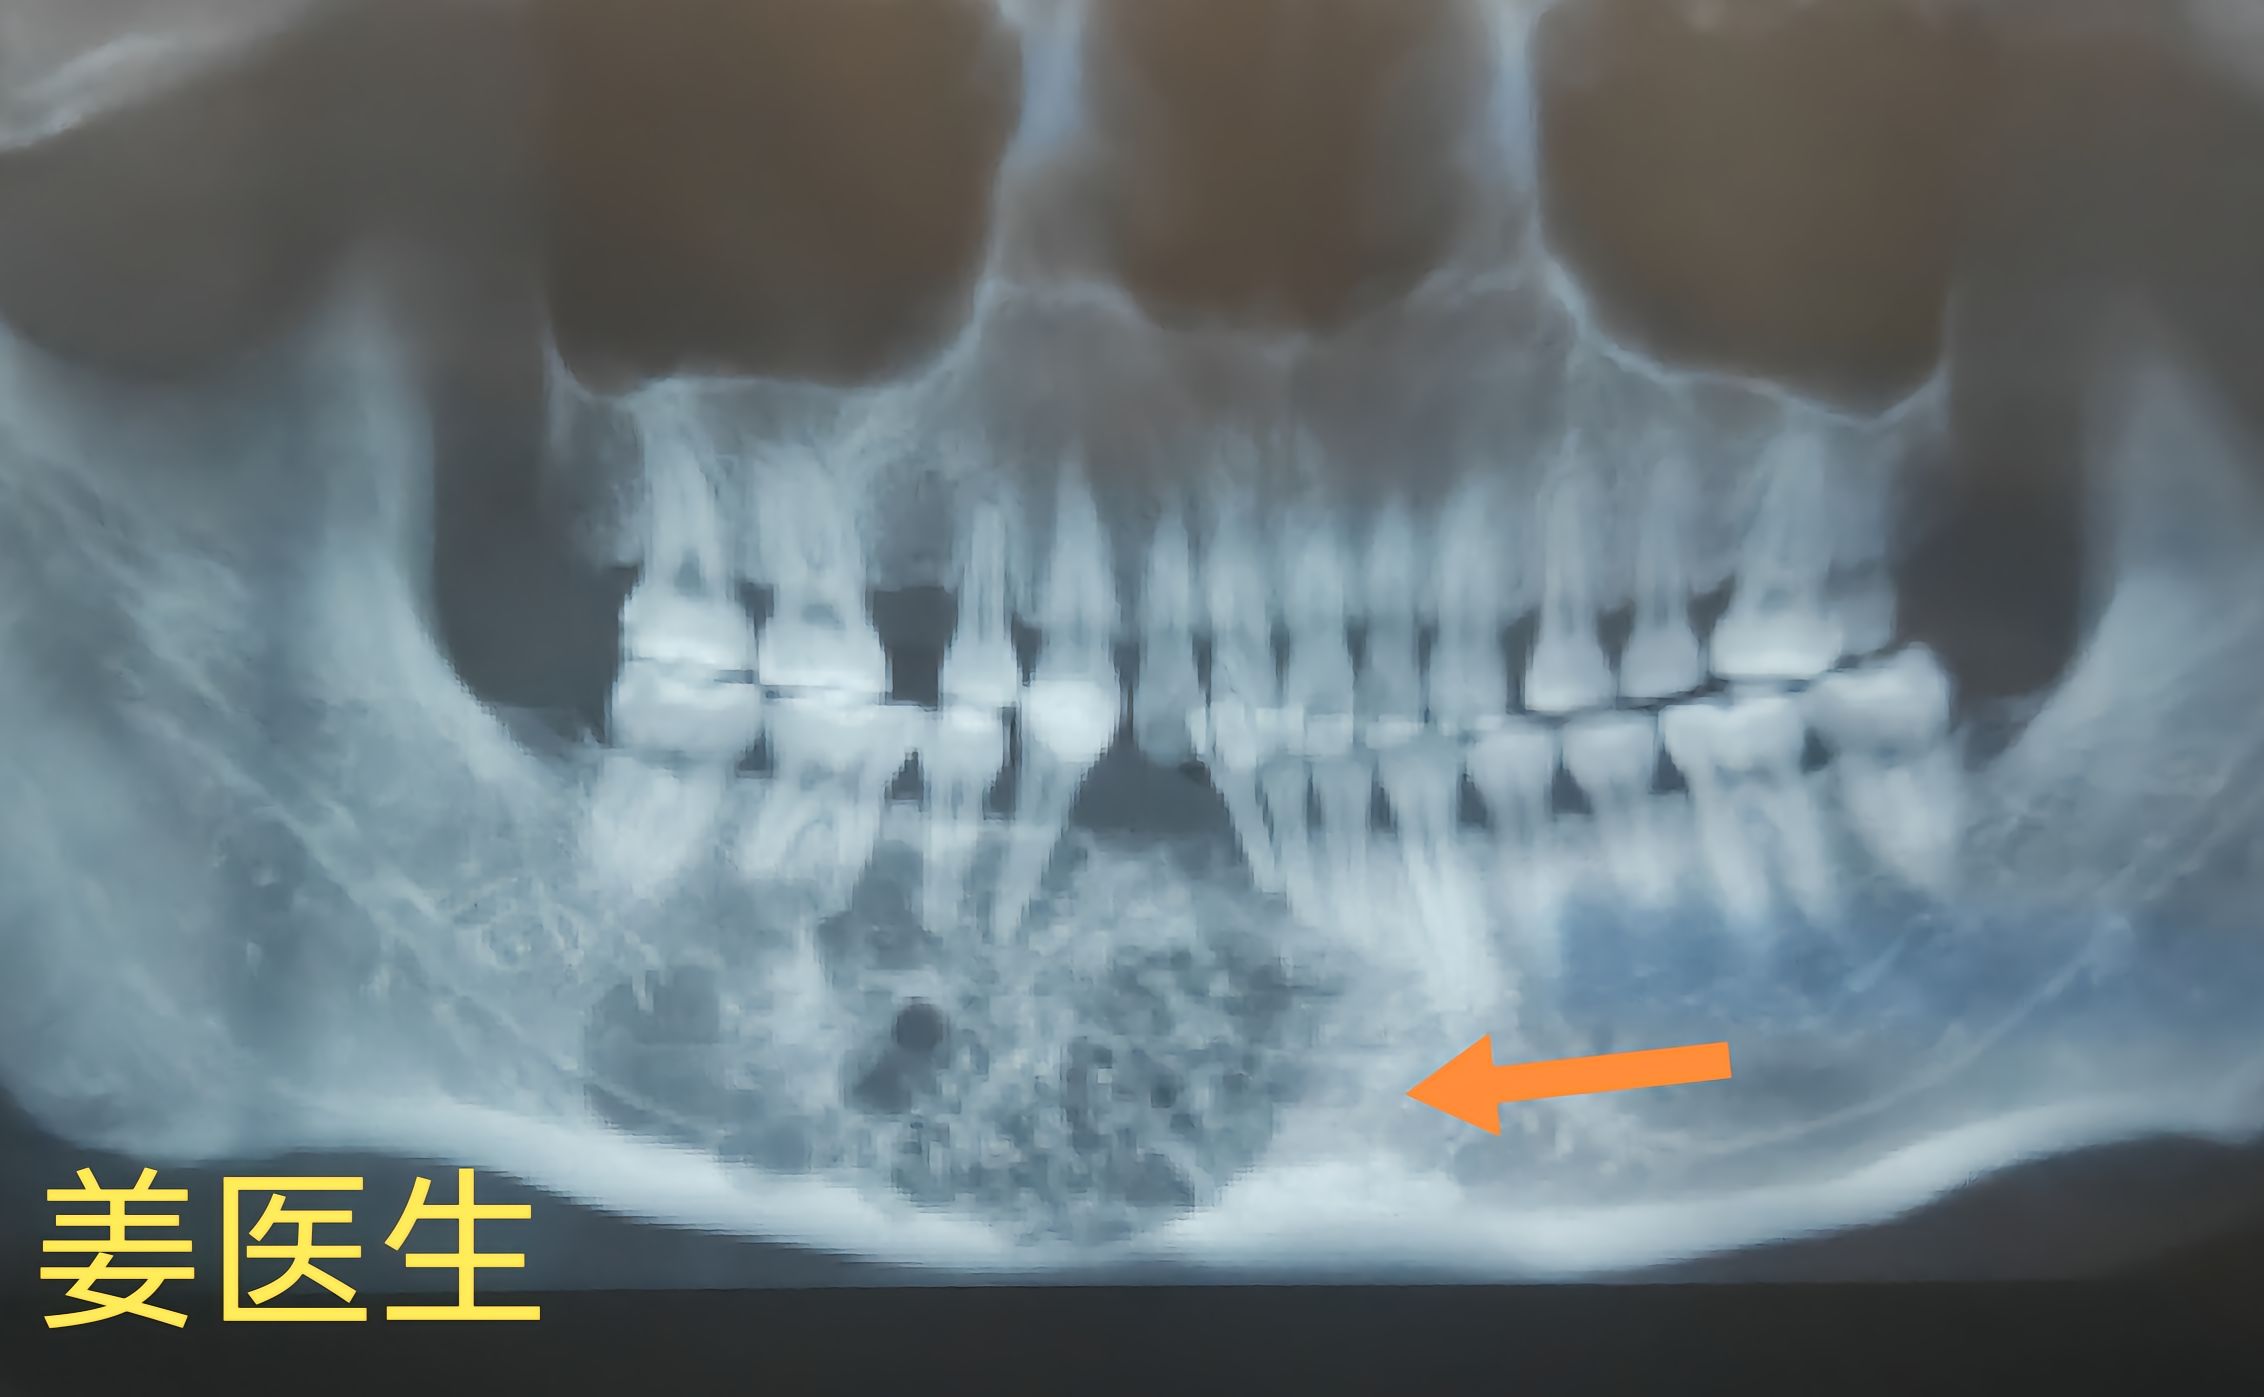

骨纤维异常增殖症

大量异常纤维组织或不成熟编织骨代替

了正常的骨组织